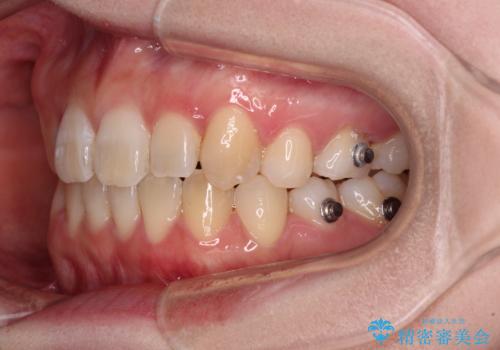

ディープバイトをインビザライン矯正で改善

- 前歯のデコボコと強い咬みしめを気にして来院された患者様です。

インビザラインを用いて、前歯の叢生を解消するとともに、ディープバイトを改善していくこととしました。

上顎に乳歯が左右1本ずつ残っていたため、若干咬み合わせに不具合が残りましたが、強い咬合力の原因であったディープバイトをしっかりと改善することができました。